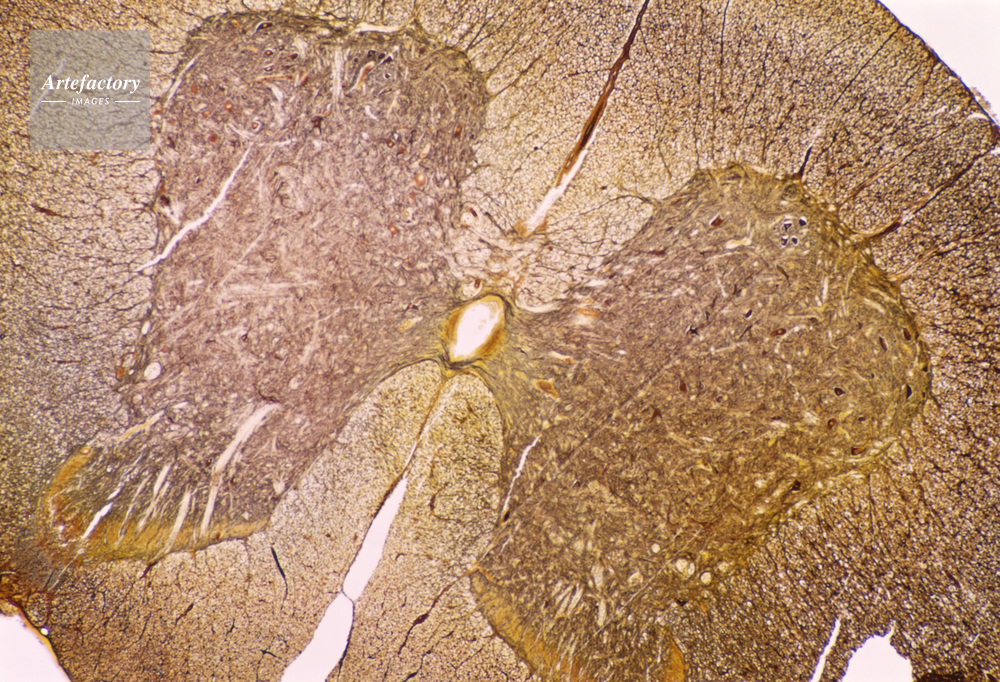

| 作品タイトル | 顕微鏡写真 | モデルリリース | なし | |

| キャプション | 脊髄,猫,20倍 | 制限事項 | ||